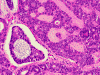

Panel A is a low-magnification photo taken at the edge of the tumor that shows tumor invasion into the surrounding salivary gland tissue. Well formed cribiform arrangment by tumor cells are show in panel B, C, and D; a fibrous stroma can be well appreciated in these photographs. Eosinophilic basement membrane like material can be well recognized in panel E; mucoid material containing microcysts are well illustrated in panel D and F. The myoepithelial component are recognized by strong immunoreactivity for calponin and smooth muscle actin (SMA) in panel G an H; note that the luminal epithelial cells do not have such immunoreactivity. Strong immunoreactivity of the tumor cells for pancytokeratin are well demonstrated in panel I

The histologic features are well illustrated in this case. In general, ADCC is a malignant tumor that is clearly invasive at macroscopic and microscopic levels. Grossly, they are usually fibrous mass with invasion into the surrounding tissue. The stroma of ADCC is typically fibrotic. The common histologic patterns are the cribiform pattern, tubular pattern and solid pattern. The less common pattern are the spindle cell pattern, trabecular pattern and solid type with comedo-type necrosis. Common histologic features are cribriform or microcystic architecture with relatively uniform cells, with small, hyperchromatic nuclei, scant cytoplasm, somewhat nulcear molding and indistinct cytoplasmic border. These cells are considered as myoepithelial differentiation.  A second cell type can be recognized as somewhat larger, with more abundant cytoplasm and less dense nuclear chromatin. These cells are thought to represent ductal epithelial cells. The ductal cells give rise to real tubular structures that contain bluish mucoid material; these cells are immunoreactive for carcinoembryonic antigen (CEA), epithelial membrane antige  (EMA), keratin, and S-100 protein. The myoepithelial cells may arrange in solid sheets and also give rise to microscystic structures containing hyalinized eosinophilic basement membrane-like material. They bear immunoreactivity for calponin, muscle specific actin, and low molecular weight cytokeratin. They are also positive for S-100 protein but are usually less strong than the ductal cells in the same tumor. Many ADCC also express C-kit (CD117) 2, especially in solid type. PAS (+) basement membrane-like material is seen in the pseudocyts and mucin in the true ducts. Perineural invasion is the rule. The tumor cells are highly proliferative and a Ki-67 labeling index over 20% is not uncommon.